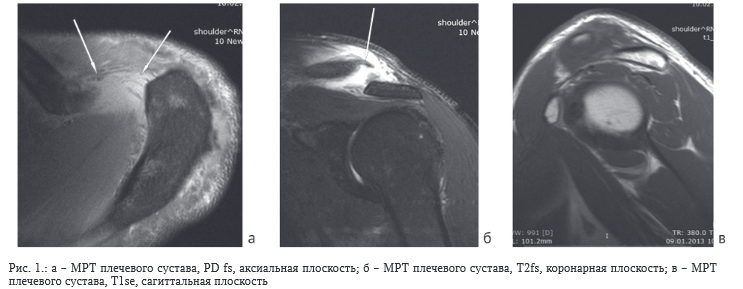

Представьте себе: врач‚ у которого есть сотни‚ а то и тысячи изображений МРТ‚ которые нужно проанализировать. Каждый снимок содержит тонкую информацию‚ которую человеческому глазу трудно уловить. Именно здесь на помощь приходит ИИ. Обученные алгоритмы могут выявлять даже самые незначительные аномалии‚ что позволяет врачам выявлять заболевания на ранних стадиях и начинать лечение вовремя.

Традиционный анализ МРТ-изображений – это трудоемкий и времязатратный процесс‚ требующий от врачей высокой квалификации и опыта. Человеческий фактор играет огромную роль‚ и даже самые опытные специалисты могут допускать ошибки или пропускать важные детали. ИИ‚ напротив‚ способен анализировать изображения с высокой скоростью и точностью‚ минимизируя риск ошибок и освобождая врачей от рутинной работы.

Более того‚ ИИ может выявлять паттерны и корреляции‚ которые не видны человеческому глазу. Это особенно важно при диагностике сложных заболеваний‚ таких как рак‚ болезнь Альцгеймера и рассеянный склероз. Ранняя диагностика этих заболеваний имеет решающее значение для успешного лечения и улучшения качества жизни пациентов.